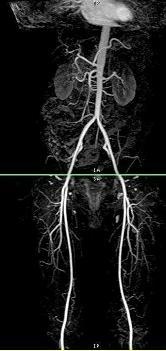

Multi Station is a GE protocol that is an alternative to QuickSTEP. It provides automatic table movement and switching of coils between stations for peripheral vascular run-offs. It allows you to prescan at multiple stations to optimize image quality and it properly annotates image locations based on the landmark. Therefore, this protocol allows imaging of multiple phases of contrast enhancement at multiple anatomical locations typically with one contrast injection. It can be performed in conjunction with a bolus triggering technique, such as SmartPrep or Fluoro Trigger.

The Multi Station sequence is acquired following the optional acquisition of a localizer meta-series. A meta-series consists of multiple series linked together. The localizer meta-series is a 3-Plane localizer that acquires several series, at different locations, across the anatomy of interest. The localizer images are used for defining the scan locations for the sequence. It is easier to save the localizers as your sites protocols when they are separate series, i.e., not linked. The meta-series can be prescribed from any localizer series. You may chose to acquire a TOF acquisition as a localizer rather than a 3-Plane Localizer acquisition.

At the time of contrast injection, the meta-series is initiated with the Scan enabled. For Fast 3D TOF sequences, the first station can be initiated using SmartPrep or Fluoro Trigger. When the bolus is detected, the 3D volume at station 1 is acquired. Upon completion of the first station, the table moves and the volume at station 2 is acquired. The system automatically moves the table and initiates data acquisition until all stations are acquired.